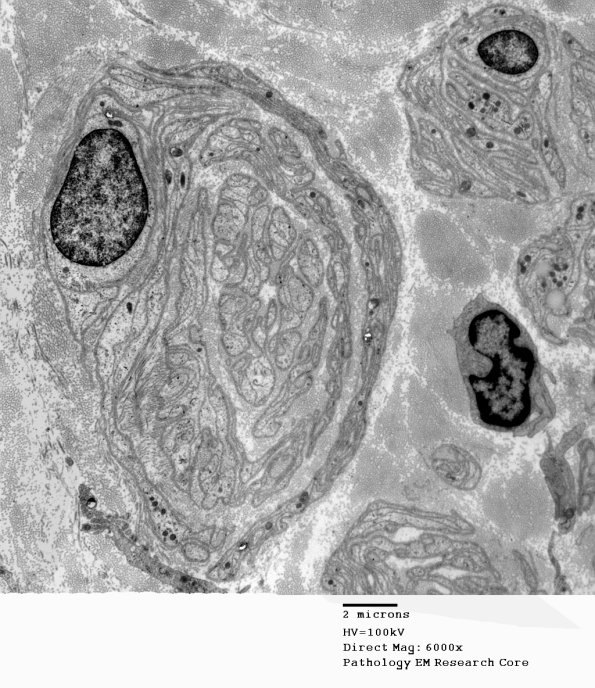

Here the POB is not so much a concentric structure but a more compressed collected mass of Schwann cell derived numerous processes. (electron micrographs)